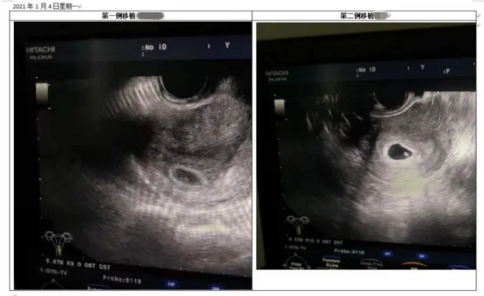

“试管一次顺利了,终究有好孕了!”4日,B超确定宫内妊娠,并顺利看见胎心的侯女士、黄女士兴奋地迎来怀孕喜讯。记者今(6)日从北方医科大学顺德医院